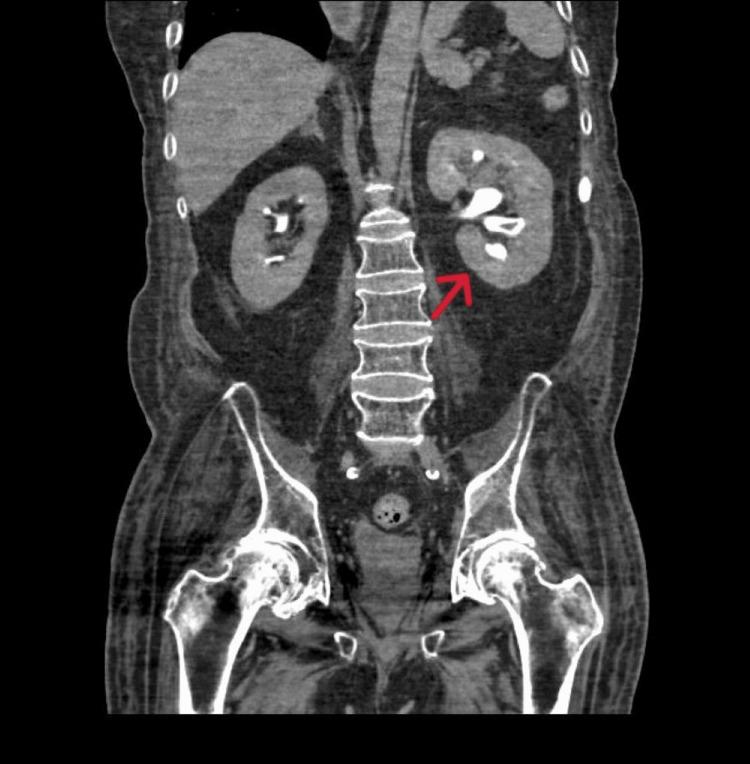

Sodium-glucose Co-transporter-2 Inhibitors Causing Fungemia and Renal Abscess.钠-葡萄糖协同转运蛋白2抑制剂导致真菌血症和肾脓肿

JCEM Case Rep. 2024 Feb 1;2(2):luae010. doi: 10.1210/jcemcr/luae010. eCollection 2024 Feb.